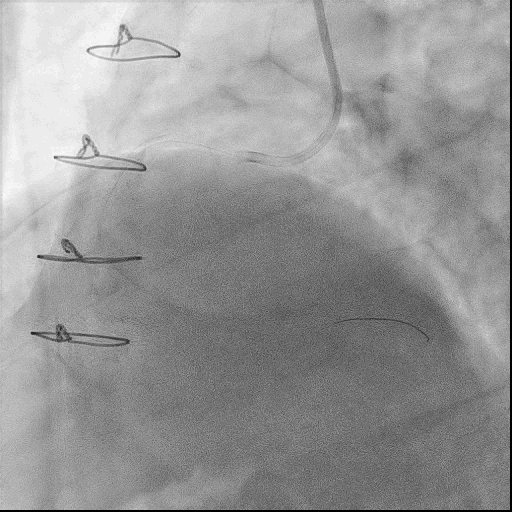

术中,球囊扩张RCA中远段后出现夹层,使用球囊压迫后复查造影TIMI血流3级,故结束手术。

术后小结:

该患者为右冠开口齐头闭塞病变,无残端,同时自身侧支形成不佳,侧支循环显影微小,提供RCA中段血流,故杜绝了逆向开通RCA-CTO病变的可能,正向为唯一策略,这使得术者处于一个非常被动的处境。葛雷教授凭借其高超的技术和丰富的经验,经过导丝升级后成功通过闭塞段开通RCA-CTO病变,显示了葛雷教授团队精湛的手术技术和默契的团队配合,同时也希望能为苦练CTO技艺的介入医师们带来一些启发。